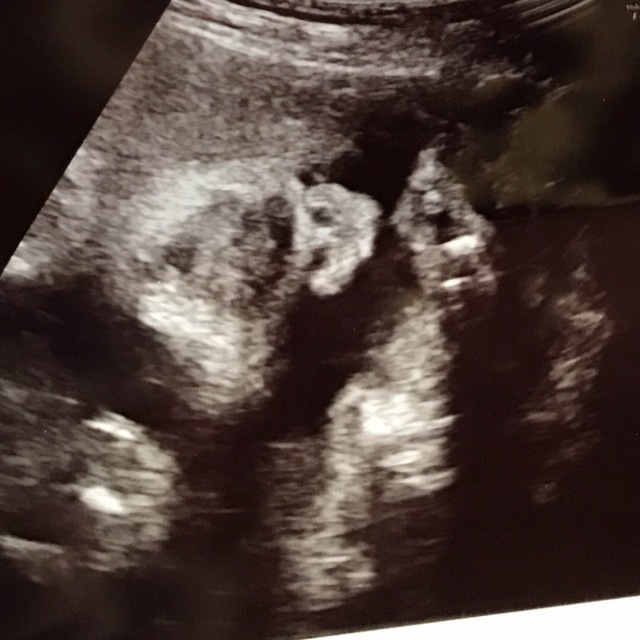

31週2日(31w2d・男の子)|花織 さん(23歳)

エコー写真撮影時のエピソード:

出産自体初めてのことで、 20代で子どもを産むことに色々不安を抱いていました。ですが、このエコーを見たとき、 初めて手がハッキリと見えて、小さいのにすごくしっかりしてることがわかりました。

母親としての実感が芽生えてはいましたが、改めて子どもを育てて行くという実感を感じることが出来ました。

このエコーのお陰ですごく元気づけられ、 産休に入るまでの間も仕事を続けることができ、 出産の一週間前まで働きました。 無理することはしないでできることをしながら 生まれてくる子どもの為に働けました。この時、 見えた手はすごく私に勇気をくれました。